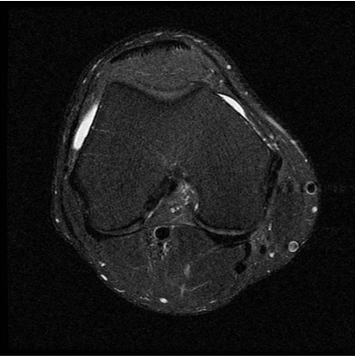

1:28 minConventional

384 x 256 (4 NEX)

3:00 minIAI (Innovative AI)

384 x 256 (2 NEX)

1:29 minReduced Scan Time

384 x 256 (2 NEX)

1:29 minConventional